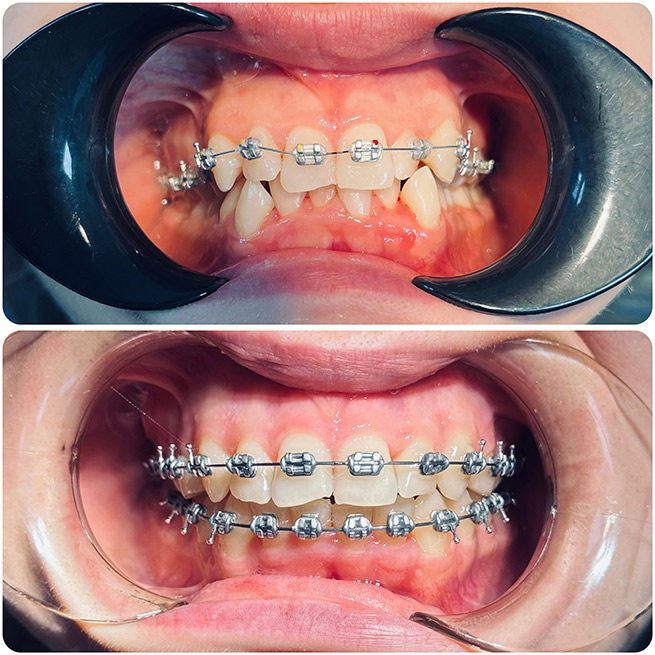

Брекет-системи – класичне та ефективне рішення для виправлення прикусу та вирівнювання зубів. Я працюю з:

- Металевими брекетами (надійні та доступні);

- Керамічними брекетами (естетичний варіант);

- Самолігуючими брекетами (металеві та керамічні);